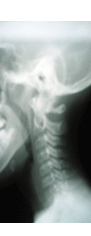

Upper Cervical Chiropractic (UpC): The upper neck area is the most critical area of the spine, where the nervous system can be affected. In this area, spinal cord compression can exist as a result of misalignment of the atlas and/or axis vertebrae. Dr. Canepa feels that most specialists have overlooked this condition, and has focused his career around treating it.